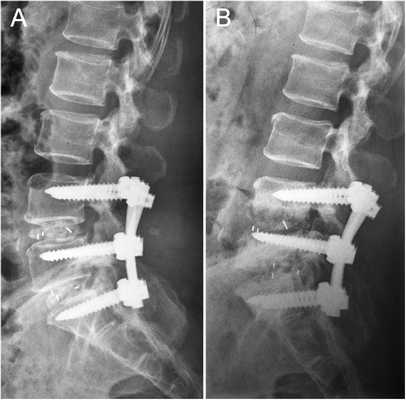

Стабилизация поясничного отдела.

Часто возникает необходимость сочетать декомпрессионные хирургические вмешательства с установкой стабилизирующей позвонки системы. Это является надежным залогом устранения риска возникновения или уже существующей нестабильности позвонков.

Стабилизирующие операции выполняют вторым этапом после устранения давления на нервно-сосудистые образования. Они заключаются в соединении склонных к смещению позвонков между собой специальными конструкциями жесткой или динамической фиксации, что невозможно эндоскопическим путем. Поэтому при возникновении необходимости в установке стабилизирующей системы декомпрессию позвоночника выполняют посредством операций с микроскопом.

Жесткие стабилизирующие системы

Системы жесткой фиксации подразумевают установку в межпозвонковое пространство костного трансплантата (обычно взятого из подвздошной кости пациента) или специального искусственного кейджа с последующим монтажом на два и более соседних позвонка металлической конструкции. В результате они обездвиживаются и со временем сращиваются между собой, т. е. происходит спондилодез.

Метод позволяет полностью устранить сегментарную нестабильность позвоночника, но при необходимости фиксации одновременно большого количества позвонков провоцирует уменьшение возможной амплитуды движений.

Жесткая стабилизация подразумевает использование техники транспедикулярной фиксации или транскутанной стабилизации. Они очень похожи между собой и отличаются одинаковой эффективностью, но последняя обладает лучшим косметическим эффектом, поскольку все манипуляции осуществляются через точечные проколы мягких тканей.

Суть метода состоит в применении специальных титановых винтов и пластин. Винты вкручиваются в точку пересечения поперечных отростков позвонка с суставными по обеим сторонам позвонка. Таким образом, фиксируется минимум 2 позвонка, хотя в ряде ситуаций требуется стабилизация значительного большего количества позвоночно-двигательных сегментов. Через шляпки винтов пропускают титановую пластину, обеспечивающую жесткость конструкции и распределение нагрузки на нее.

Нестабильность позвоночника считается одним из распространенных заболеваний и основным методом лечения является транспедикулярная фиксация подвижного сегмента, декомпрессивная ляминэктомия, дискэктомия с установкой между телами позвонков кейджа который фиксирует сегмент на 360 градусов (золотой стандарт). В подобных ситуациях метод обеспечивает надежный спондилодез у 80- 95% пациентов. ТПФ является одним из наиболее часто применяемых методов оперативного лечения заболеваний и травм в связи с тем, что современные хирурги стараются добиться спондилодеза на 360°. Достичь этого позволяет сочетание ТПФ с межтеловым спондилодезом, что обеспечивает высокую частоту костных сращений и отсутствие остаточной незначительной подвижности в передних отделах прооперированного сегмента. Поэтому при успешном завершении операции и правильном восстановлении пациенты гарантировано избавляются от болевого синдрома.